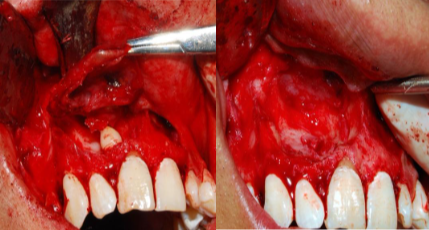

Plan de tratamiento:

Se procedió a realizar la exéresis quirúrgica de la lesión mediante un acceso vestibular trapezoidal, con previa anestesia local con lidocaína 2% + epinefrina. Se expuso el quiste, el cual es abierto y enucleado en su totalidad junto con el órgano dentario involucrado, se limpió el defecto óseo ocasionado por el quiste con clorhexidina al 0.12% y, finalmente, se reposicionó el colgajo con puntos simples de sutura (Figura 3: A y B). El tejido extraído es enviado para su estudio histopatológico definitivo, con el cual se ratificó el diagnóstico de quiste dentígero. Adicionalmente, se interconsultó con la especialidad de endodoncia, para la valoración de los dientes 11, 12 y 21 por presentar rizolisis, los cuales fueron diagnosticados vitales, motivo por el cual no se requirió tratamiento de conducto.

A. Exposición del quiste.

B. Enucleación del quiste.